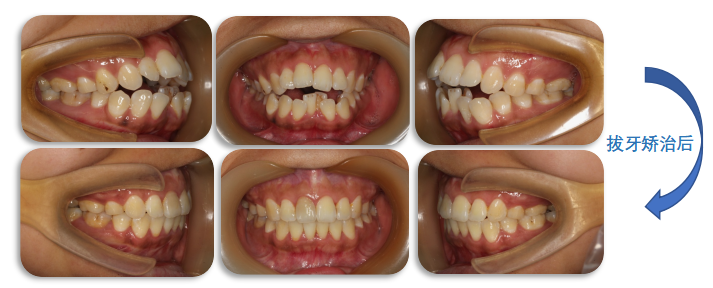

治疗前

拔牙治疗后

通过拔牙矫治,内收前牙,改善“哨牙”及突面型